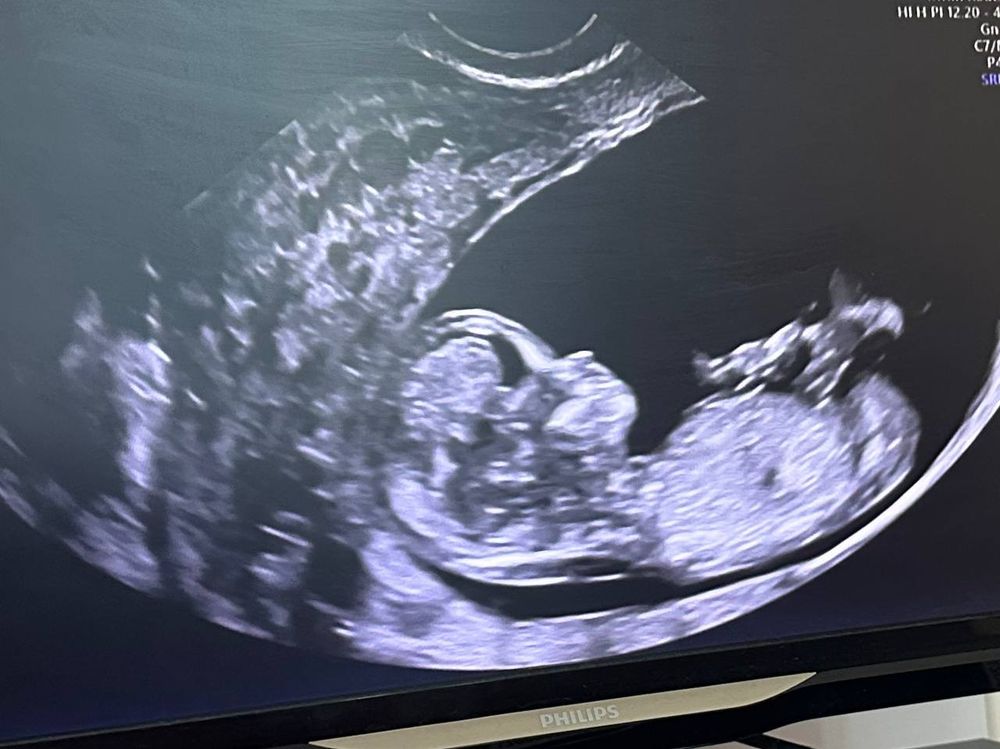

Вчера прошли скрининг, малыш замечательный и здоровый. Наслаждаюсь беременностью, никаких тревог, спокойна, счастлива. ЭКО беременность на текущий момент оказалась легкой, пусть так и будет дальше🙏🏻.

Сынуля в 11+2 был 6 см по КТР. К сыну уже обращаемся по имени, Константин❤️

11 неделек здесь, машет ладошкой.

По КТР малыш уже 12 + 3 был вчера